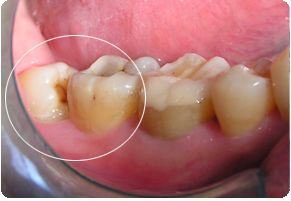

第二位患者同樣姓張,但他在25歲的年紀(jì),卻已經(jīng)被智齒疼痛折磨了2年多了。小張自述,自己的智齒疼,并不是“疼起來要人命”的那種,所以才一拖再拖。但近期,小張的下頜右側(cè)牙齦反復(fù)長膿包,因擔(dān)心病變擴(kuò)大,才終于鼓足勇氣走進(jìn)了口腔科。醫(yī)師在檢查小張口內(nèi)情況時(shí)看到,該患者下頜右側(cè)第二磨牙牙冠表面完整,但在頰側(cè)牙齦位置處,可見約5mm直徑的膿包,膿包下,一顆牙冠傾斜部分微微露出的智齒隱約可見,而這兩顆牙齒之間,竟有著大量嵌塞的食物,已然形成齲洞!并且第二磨牙周圍骨質(zhì)被破壞嚴(yán)重,牙齒已經(jīng)是“懸浮”在牙槽窩內(nèi),這顆看似完整的牙齒因?yàn)橹驱X給予的阻力和齲洞的存在,其實(shí)已經(jīng)不具有保留價(jià)值了,只能和智齒一起被連根拔除。